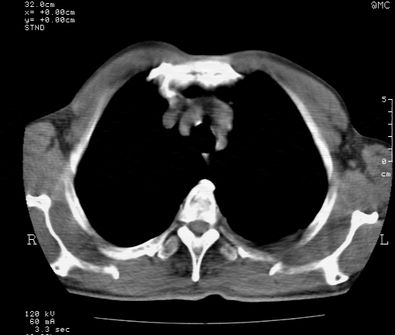

标题: CT24000:M65,胸痛,胸闷月余,既往慢支,肺气肿,肺心病 [打印本页]

标题: CT24000:M65,胸痛,胸闷月余,既往慢支,肺气肿,肺心病

1左侧胸腔积液

2左肺门站位

3双肺条索影

4右肺上叶密度增高影考虑右肺上叶肺不张,阻塞性肺炎

5纵隔内见肿大淋巴结影